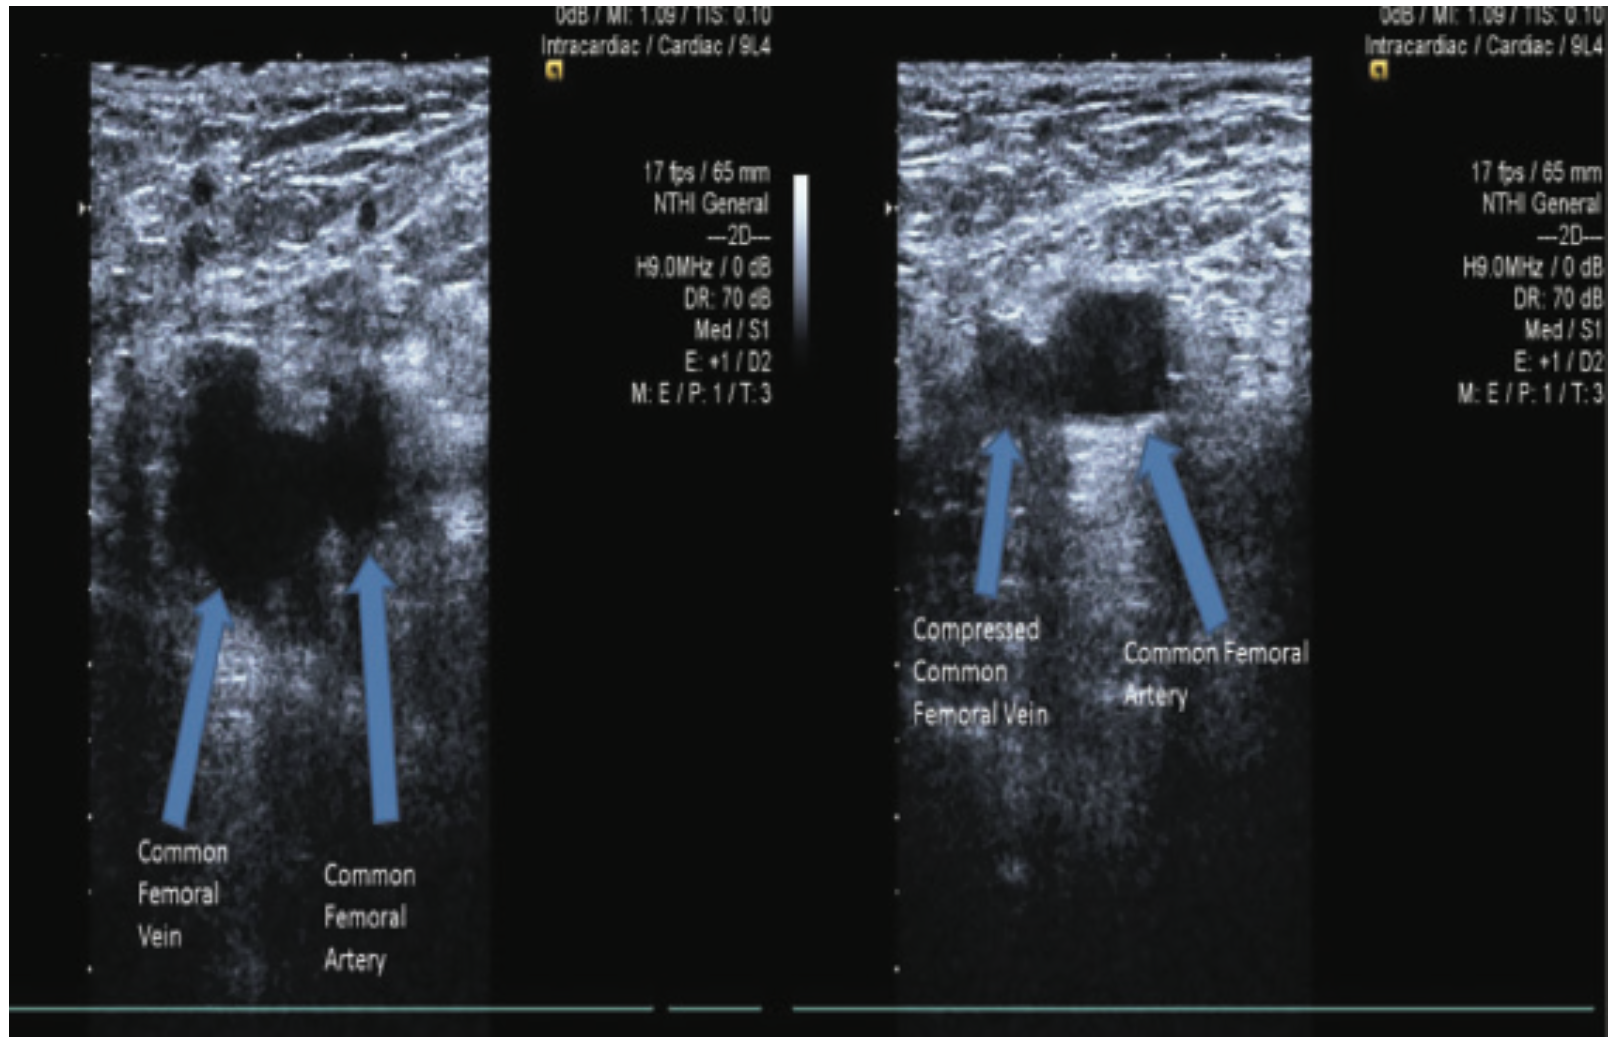

Ultrasound can be used to take static or dynamic images of a target blood vessel. However, dynamic ultrasound offers the advantage of observing vascular access in real time.3,4 Most ultrasound machines allow for short axis and long axis views to actively visualize wire and needle insertion (Figure 2). Color-flow ultrasound can confirm arterial and venous flow, and verify the patency of a target vessel. Ultrasound can also differentiate between arterial and venous structure by performing a compression test. In this test, the thinner-walled vein collapses when the probe applies pressure (Figure 3). Additionally, arterial pulsation may be visualized with US, which also helps distinguish between arterial and venous anatomy. For correct orientation of anatomy, the ultrasound probe indicator should be placed to the operator’s left side (Figure 4). Basic procedural steps for vascular access are described in Table 2.

Femoral arterial and venous access is widely used for a wide variety of procedures. For arterial access, US guidance, in conjunction with external rotation of the leg and fluoroscopic marking of the femoral head, can decrease the number of attempts for successful common femoral artery cannulation. It reduces the time to obtain access, the risk of puncturing the wrong vessel or vessel segment, and subsequent vascular complications (Figures 8-9). US guidance helps avoid punctures into the superficial femoral artery or profunda, decreases inappropriate punctures of the femoral vein, and it may prevent sticks above the inguinal ligament. Increasing US experience was associated with a reduced time required for access with US guidance, and operators with greater than 10 procedures have reduced access time and demonstrate a trend toward improved common femoral artery cannulation success.12-15 When using large-caliber sheaths for procedures such as transcatheter aortic valve replacement (TAVR) and endovascular aneurysm repair, US guidance of the vessel ensures placement of the sheath into the center of a large, disease-free vessel segment. This may help minimize procedural complications, improve the technical success of the procedure, and optimize hemostasis.